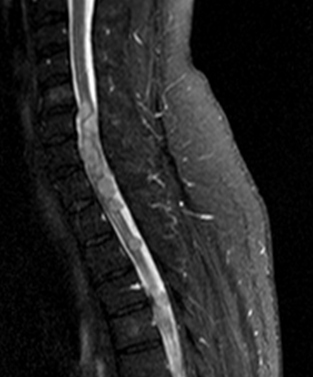

10.2.1.3. MRI:

As opposed to CT examination MRI, thanks to its superior soft-tissue contrast, is excellent for the representation of intraspinal structures. Depending on the magnetic field strength / resolution ability it is a unique imaging method of the spinal chord.

Syrinx describes the condition when cerebrospinal fluid enters the interior of the spinal cord and forms a cavity in its center in a tube or a flute- like manner. It can even be a few segments long.

MRI: only MRI can provide a definitive diagnosis by depicting the expanded region within the axis of the spinal chord as an expansile lesion showing liquor intensity on all sequences (weak T1 signal and strong on T2 weighted imaging).

MRI: segmental high T2 signal intensity lesion, which later turns into a well defined atrophy.